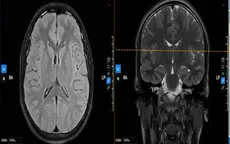

Cô gái trẻ thường xuyên lên cơn động kinh do dị dạng mạch máu não

VTV.vn - Thường xuyên đau đầu dữ dội, kèm các cơn động kinh do dị dạng mạch máu não khiến sức khỏe cô gái 28 tuổi người Campuchia ngày càng suy yếu.